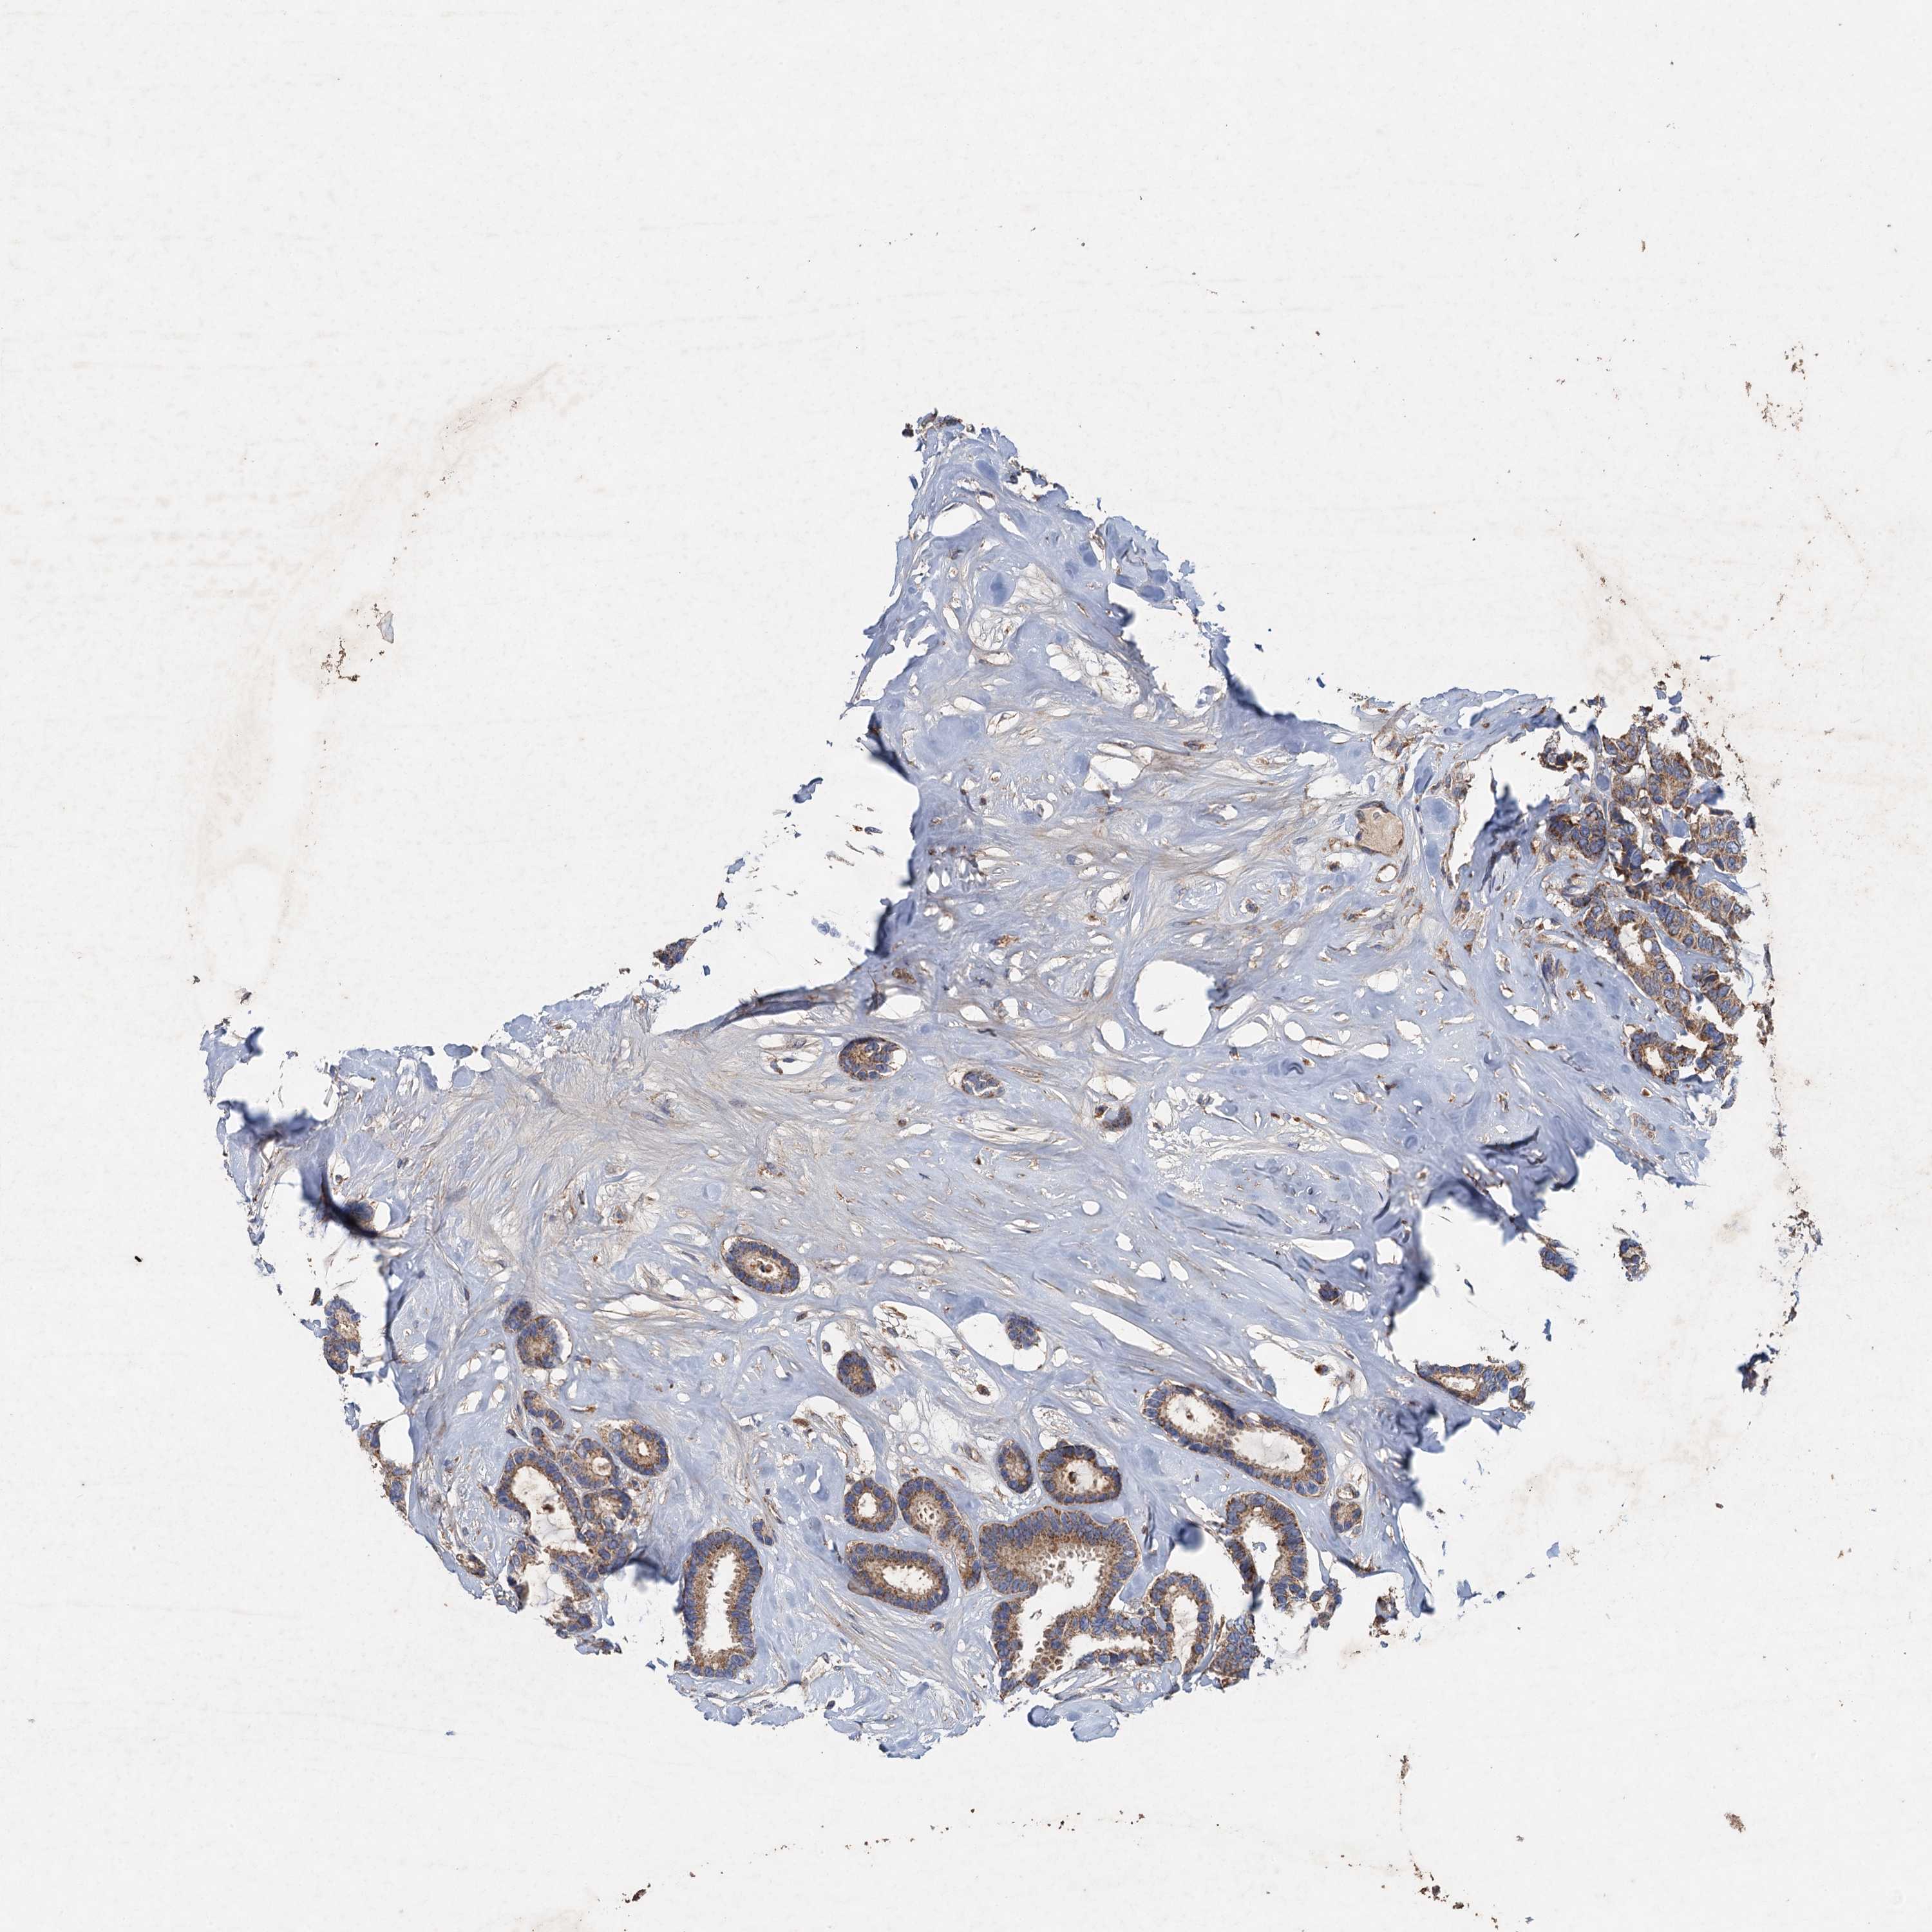

BRCA TCGA BRCA VALIDATION PROTEIN EXPRESSION